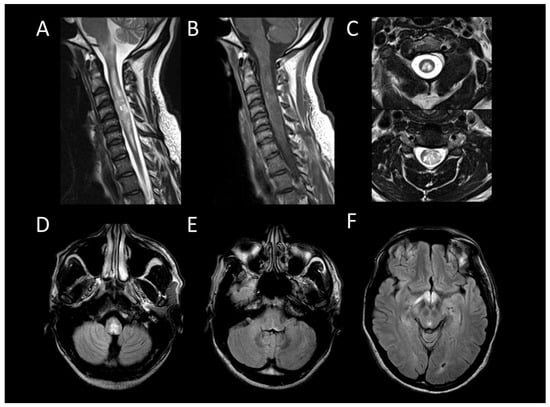

Neurosarcoidosis

Acute Demyelinating Encephalomyelitis

Neuro-Behçet’s Disease

Anti-GFAP Encephalomyelitis